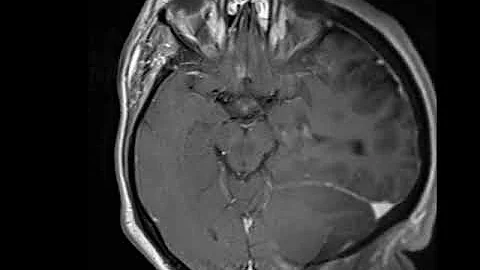

Hydrocephalus Due To Colloid Cyst Animation By Cal Shipley, M.d.

Hydrocephalus, Brainstem Herniation and Stroke due to obstruction of the Foramen of Monro by a Colloid Cyst NEU083 Related ...